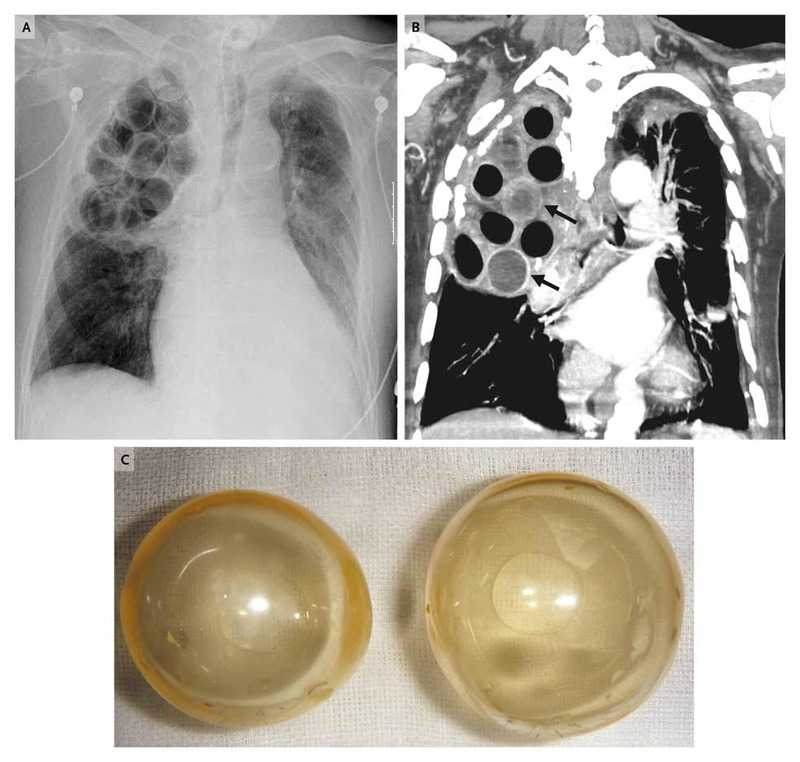

Radiographic and computed tomographic (CT) images of the chest (Panels A and B, respectively) revealed the balls, most of which were lucent (Panel C) and some of which had broken inside the pleural space.

Muddy fluid was observed inside some of the balls, which was consistent with the high-density fluid seen inside the balls on the CT image (arrows in Panel B). Pseudomonas aeruginosa was cultured from both the fluid in the balls and the patient’s blood.